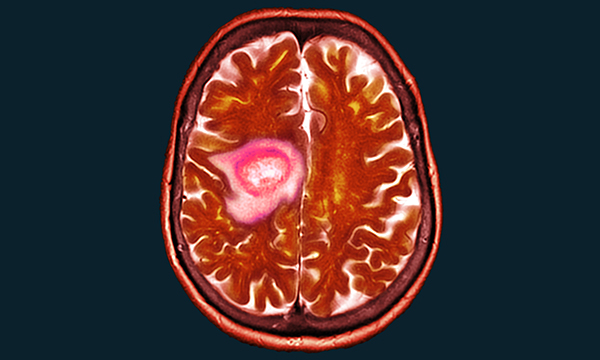

Brain tumours are rare but survival rates are low, with most life-years lost of any cancer